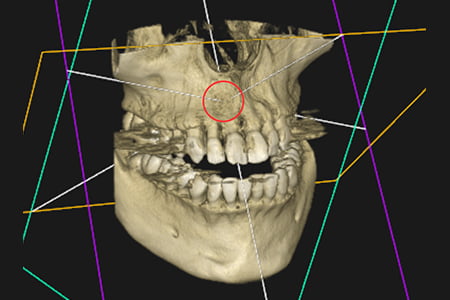

| 症状 | 左上の前歯が急に疼く様になった |

|---|---|

| 治療方針 | 大きな骨欠損を認められる為、精密根管治療を行い骨欠損部位が改善するか経過を追う |

| 治療期間 | 10ヵ月 |

| 治療費用(税込) | ¥468,600 ※2歯分 |